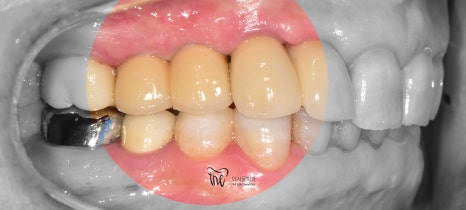

그것도, 원래 있었던 치아마냥 똑같이

재현을 해드리면서 시술 종료!

좁은 치조골 및 폭경이 충분하질 않았으며,

3개씩이나 되는 implant fixture 들을

한번에 심어야 되는데.. 그것도 나란히요.

쉽지 않았으나, 해냈습니다.